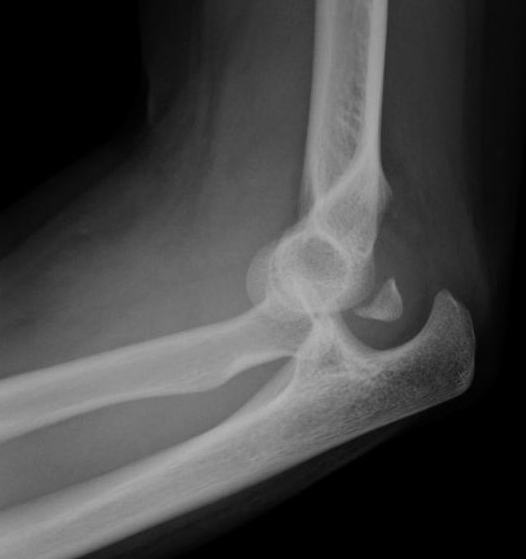

From www.orthobullets.com

Elbow Stiffness and Contractures Shoulder & Elbow Orthobullets Elbow Flexion Contracture Physical Therapy Operative management is indicated in the event of bony block to motion, congenital disease and lack of. Physiotherapy has an important role to play in the management of pain and dysfunction around the elbow joint. The elbow joint after trauma is prone to developing contractures. Flexion contractures greater than 30° or the inability to flex the elbow to at least. Elbow Flexion Contracture Physical Therapy.